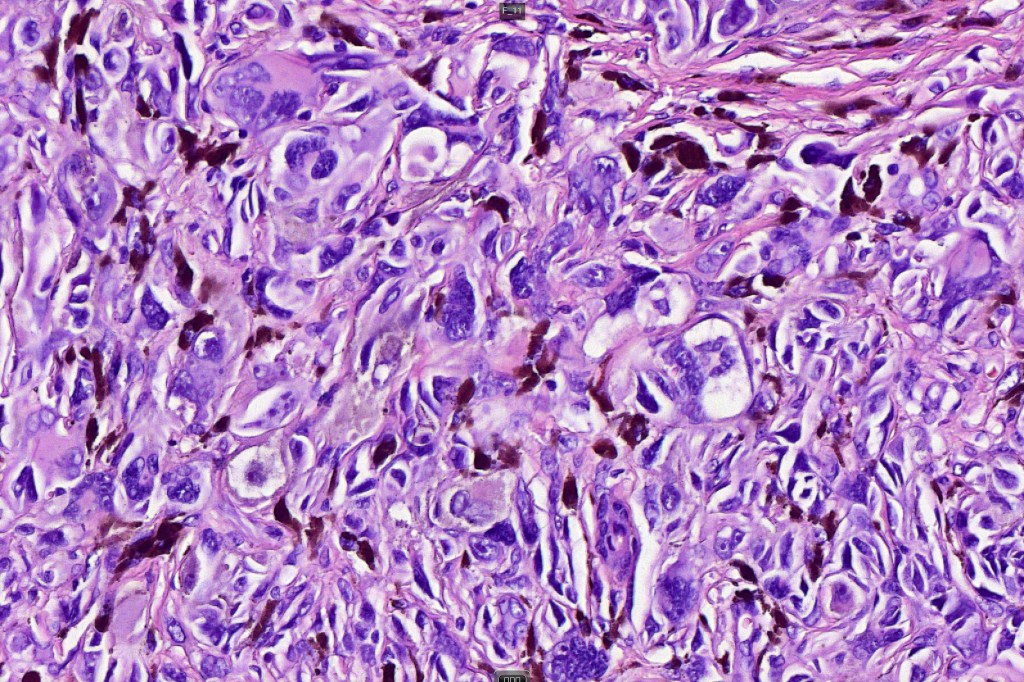

•Pleomorphism is almost invariable but affects all of the population to the same extent i.e., the cells & nuclei all look very much the same

•Spindle cell nests often display a “raining down” growth pattern

•Spindle cells have abundant cytoplasm and vesicular nuclei with small nucleoli

•Epithelioid cell variants often show greater pleomorphism and cells can frequently appear bizarre with abundant, sometimes ground glass cytoplasm and large vesicular nuclei with prominent eosinophilic nucleoli, multinucleate cells are often seen

•Intracytoplasmic pseudoinclusions commonly present in epithelioid cells

•Mitoses can brisk in younger patients and should not be taken as indicating melanoma

•Mitoses are restricted to the superficial aspect on the nevus and are never atypical